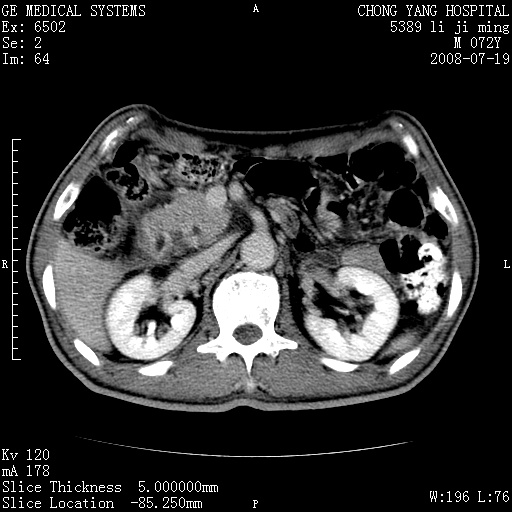

以下是引用zjzjr在2008-7-19 20:57:00的发言:[br]胰头增大,边缘模糊,周围可见渗出影,右侧肾前筋膜增厚.支持胰腺炎.

以下是引用yangyudong333在2008-7-20 6:56:00的发言:[br]胰腺增大尤以胰头明显,边缘模糊,周围可见渗出影,右侧肾前筋膜增厚,肠管於涨.支持胰腺炎

以下是引用不学无术在2008-7-19 23:15:00的发言:[br]胰腺增大尤以胰头明显,边缘模糊,周围可见渗出影,右侧肾前筋膜增厚,肠管於涨.支持胰腺炎